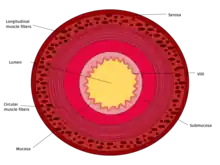

Additional images

Small intestine in situ, greater omentum folded upwards.

Tissue layers (mucosa, submucosa & muscularis)

Microanatomy

The three sections of the small intestine look similar to each other at a microscopic level, but there are some important differences. The parts of the intestine are as follows:

Digested food is now able to pass into the blood vessels in the wall of the intestine through either diffusion or active transport. The small intestine is the site where most of the nutrients from ingested food are absorbed. The inner wall, or mucosa, of the small intestine, is lined with intestinal epithelium, a simple columnar epithelium. Structurally, the mucosa is covered in wrinkles or flaps called circular folds, which are considered permanent features in the mucosa. They are distinct from rugae which are considered non-permanent or temporary allowing for distention and contraction. From the circular folds project microscopic finger-like pieces of tissue called villi (Latin for "shaggy hair"). The individual epithelial cells also have finger-like projections known as microvilli. The functions of the circular folds, the villi, and the microvilli are to increase the amount of surface area available for the absorption of nutrients, and to limit the loss of said nutrients to intestinal fauna.